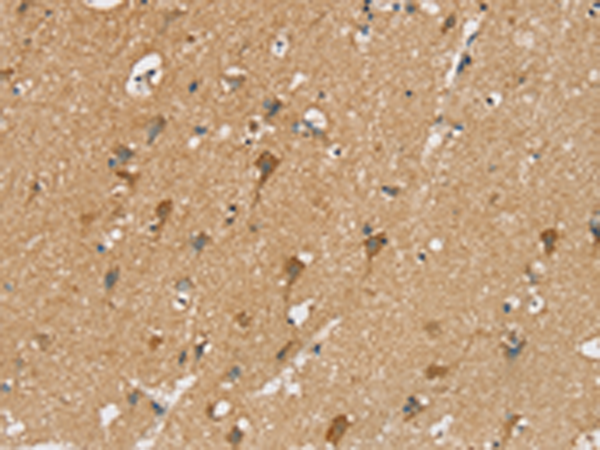

分类: 科研抗体货号: P12202别名: NCX3应用: IHC反应种属: Human, Rat